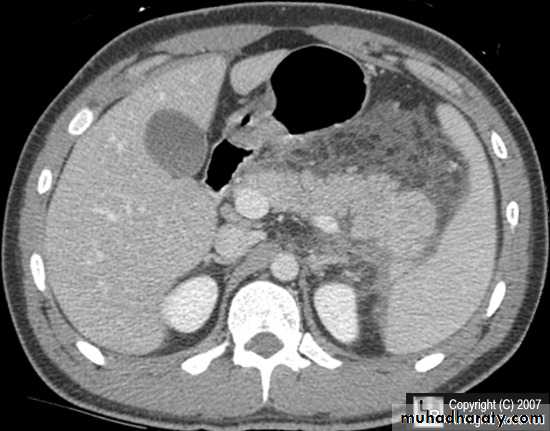

Secondary metastasis in the liver

Multiple rounded hypo density areas of different density , shape & different size .

Pattern of enhancement is either uniform , target or bulls eye pattern .

Hepato megaly .